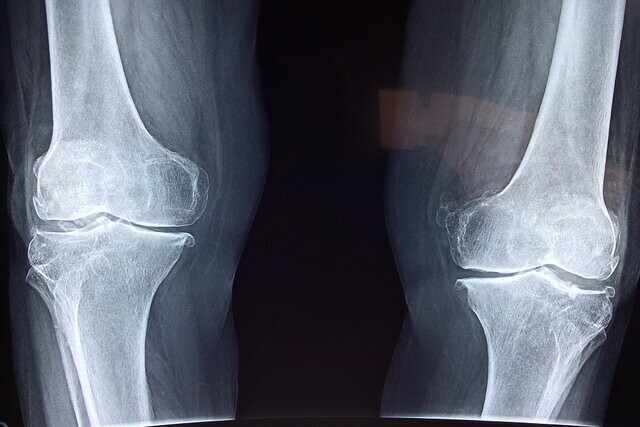

فوق تخصص بیماری‌های روماتولوژی با اشاره به اهمیت پیشگیری و تشخیص زودهنگام پوکی استخوان گفت: این بیماری به کاهش مواد معدنی و آلی در بافت استخوان گفته می‌شود و متأسفانه اصلی‌ترین علامت آن، بی‌علامتی است؛ یعنی در بسیاری از موارد بیمار هیچ نشانه‌ای ندارد و استخوان‌ها به‌تدریج و بی‌صدا دچار ضعف و پوکی می‌شوند، همانند موریانه‌ای که چوب را آهسته می‌خورد.

آذربانی در خصوص روش‌های تشخیص بیماری توضیح داد: تشخیص پوکی استخوان با انجام سنجش تراکم استخوان (BMD) یا دگزا (DEXA) انجام می‌شود. این تست ساده و بدون درد، میزان تراکم مواد معدنی در استخوان را می‌سنجد و با کمترین میزان اشعه انجام می‌شود. حتی در زنان باردار نیز در شرایط خاص قابل انجام است. همه‌ خانم‌های بالای ۶۵ سال و آقایان بالای ۷۰ سال باید بدون هیچ پیش‌شرطی این تست را انجام دهند.

وی در توضیح تفاوت پوکی استخوان با نرمی استخوان افزود: در پوکی استخوان، هم مواد آلی و هم مواد معدنی کاهش می‌یابد، اما در نرمی استخوان عمدتاً مواد معدنی دچار کاهش می‌شوند.

وی در پایان گفت: بهترین توصیه برای پیشگیری از پوکی استخوان، داشتن تغذیه سالم، پرهیز از فست‌فود، فعالیت بدنی منظم، عدم مصرف دخانیات و مشورت با پزشک برای بررسی وضعیت تراکم استخوان است. پوکی استخوان بیماری خاموشی است که اگر به‌موقع تشخیص داده شود، قابل کنترل و در بسیاری از موارد قابل درمان است.